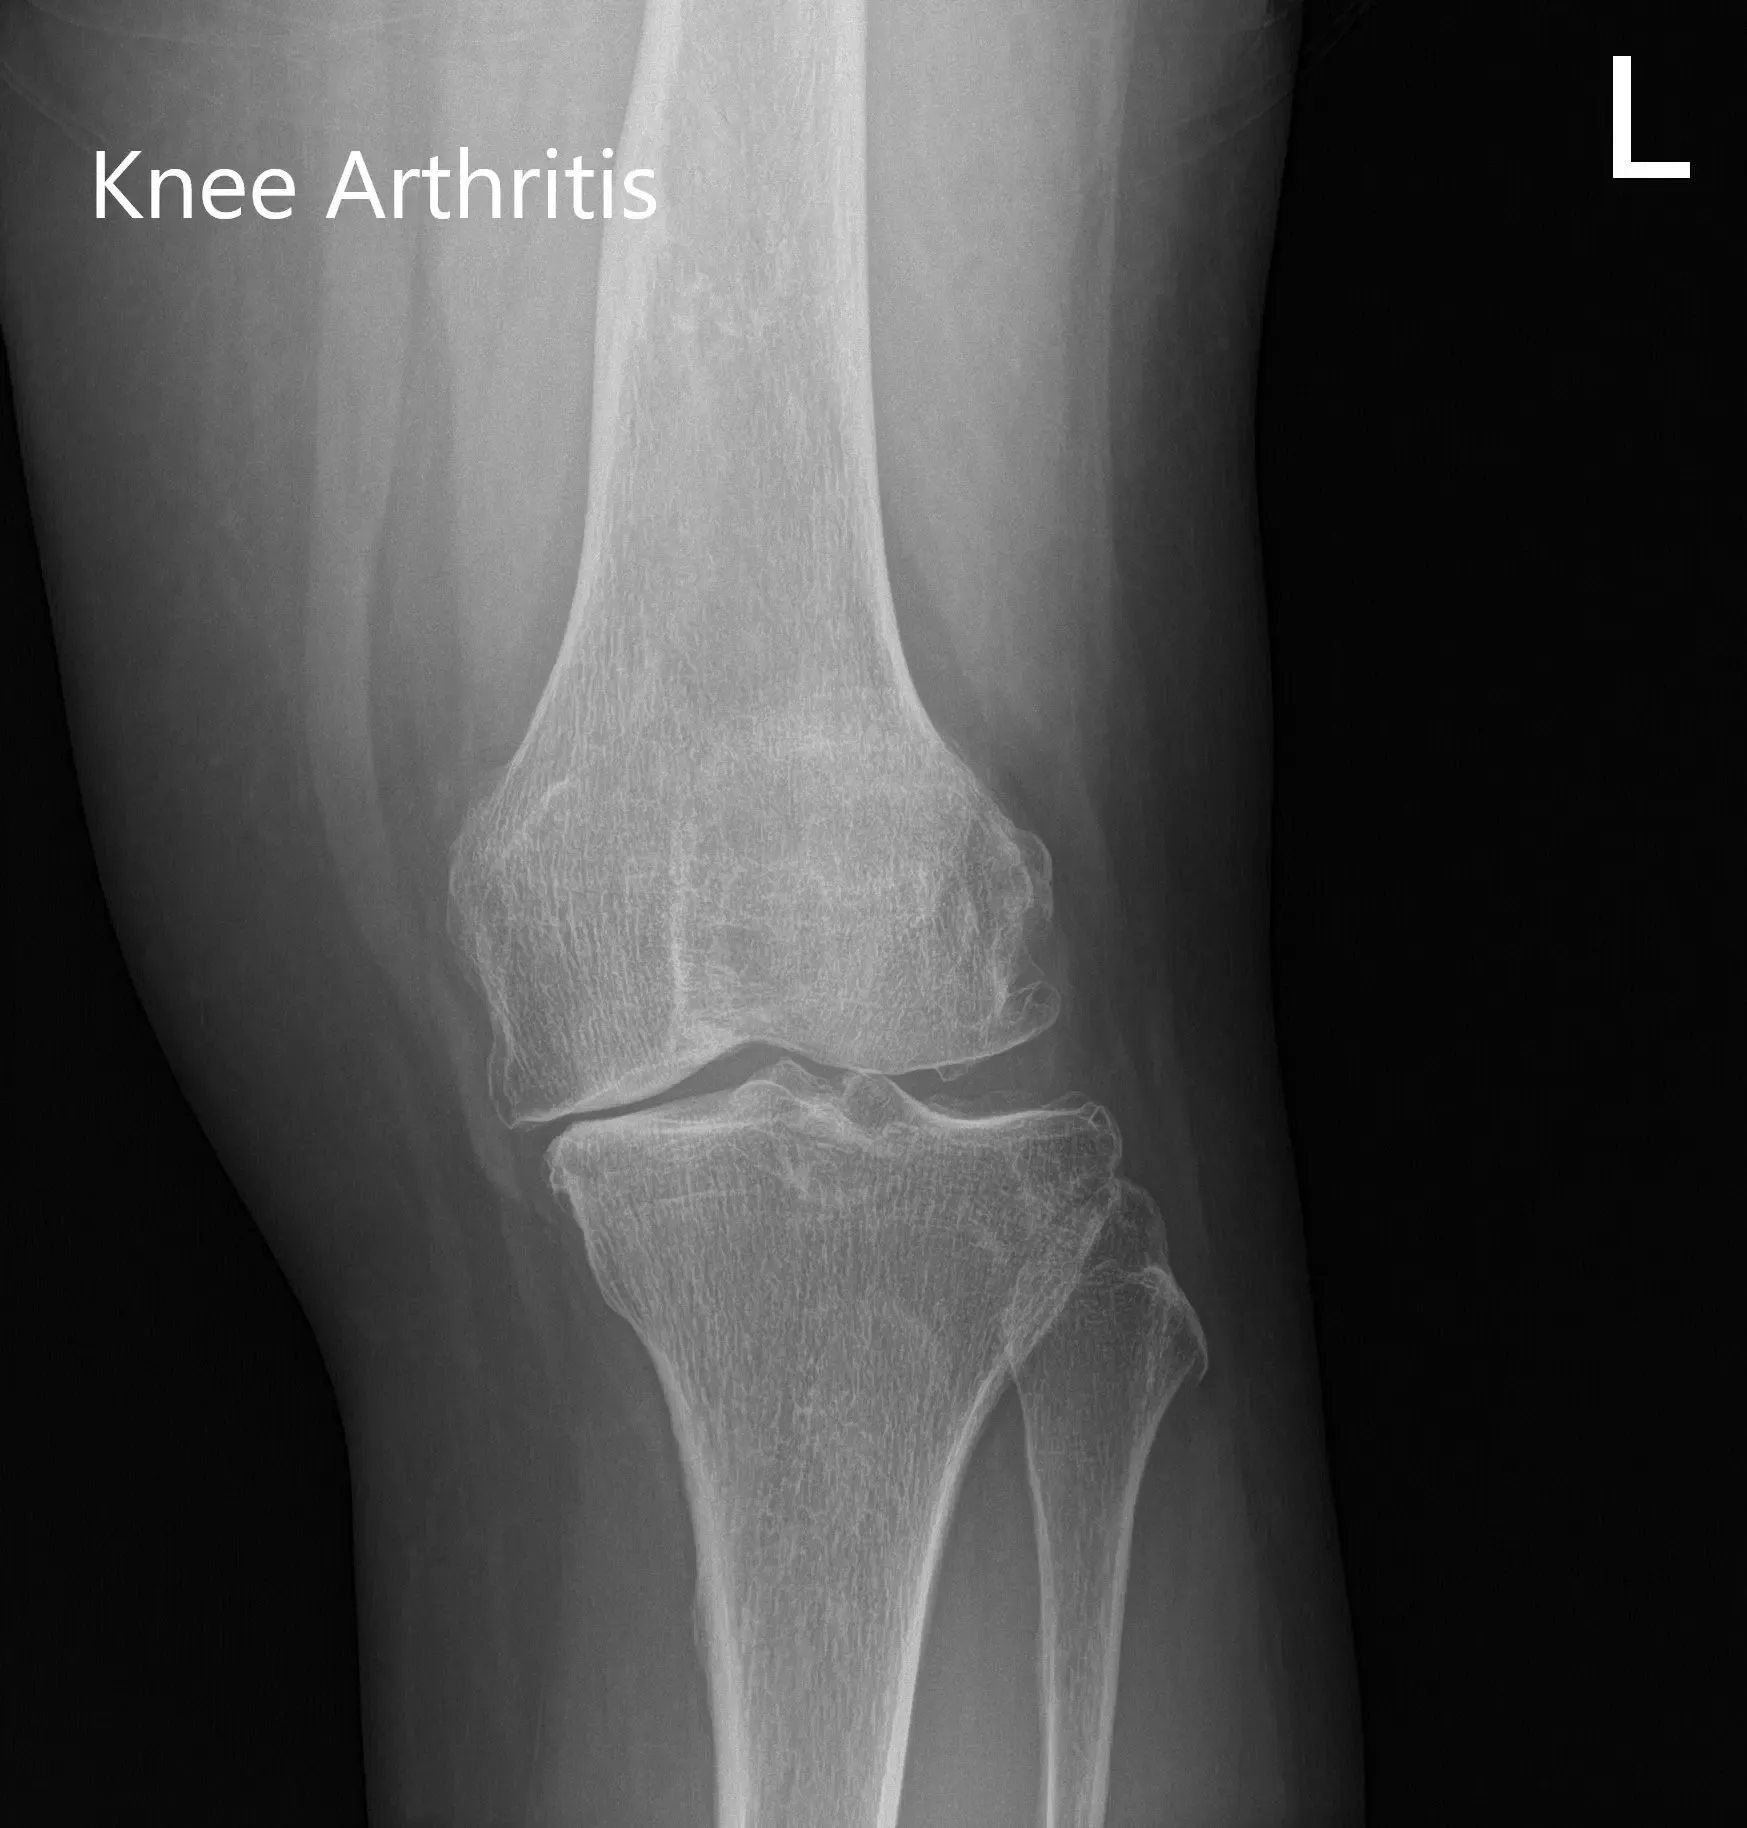

Estaba estresado por el dolor que últimamente había empezado a perturbar su sueño. Dijo que el dolor limitaba el estilo de vida. Los estudios de imagen revelaron osteoartritis tricompartmental severa. Se discutieron en profundidad con el paciente diversas opciones de manejo no quirúrgico y quirúrgico. Se le consideró candidato para un reemplazo total personalizado de rodilla izquierda.

Radiografía preoperatoria que muestra imágenes AP e laterales de la rodilla izquierda